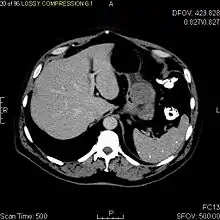

CT scanning is often undertaken (see the radiology section).

The purpose of radiologic imaging is to locate the lesion, evaluate for signs of invasion and detect metastasis. Features of GIST vary depending on tumor size and organ of origin. The diameter can range from a few millimeters to more than 30 cm. Larger tumors usually cause symptoms in contrast to those found incidentally which tend to be smaller and have better prognosis.[4][13] Large tumors tend to exhibit malignant behavior but small GISTs may also demonstrate clinically aggressive behavior.[14]

Barium fluoroscopic examinations and CT are commonly used to evaluate the patient with abdominal complaints. Barium swallow images show abnormalities in 80% of GIST cases.[14] However, some GISTs may be located entirely outside the lumen of the bowel and will not be appreciated with a barium swallow. Even in cases when the barium swallow is abnormal, an MRI or CT scan must follow since it is impossible to evaluate abdominal cavities and other abdominal organs with a barium swallow alone. In a CT scan, abnormalities may be seen in 87% of patients and it should be made with both oral and intravenous contrast.[14] Among imaging studies, MRI has the best tissue contrast, which aids in the identification of masses within the GI tract (intramural masses). Intravenous contrast material is needed to evaluate lesion vascularity.

Preferred imaging modalities in the evaluation of GISTs are CT and MRI,[16]: 20–21 and, in selected situations, endoscopic ultrasound. CT advantages include its ability to demonstrate evidence of nearby organ invasion, ascites, and metastases. The ability of an MRI to produce images in multiple planes is helpful in determining the bowel as the organ of origin (which is difficult when the tumor is very large), facilitating diagnosis.